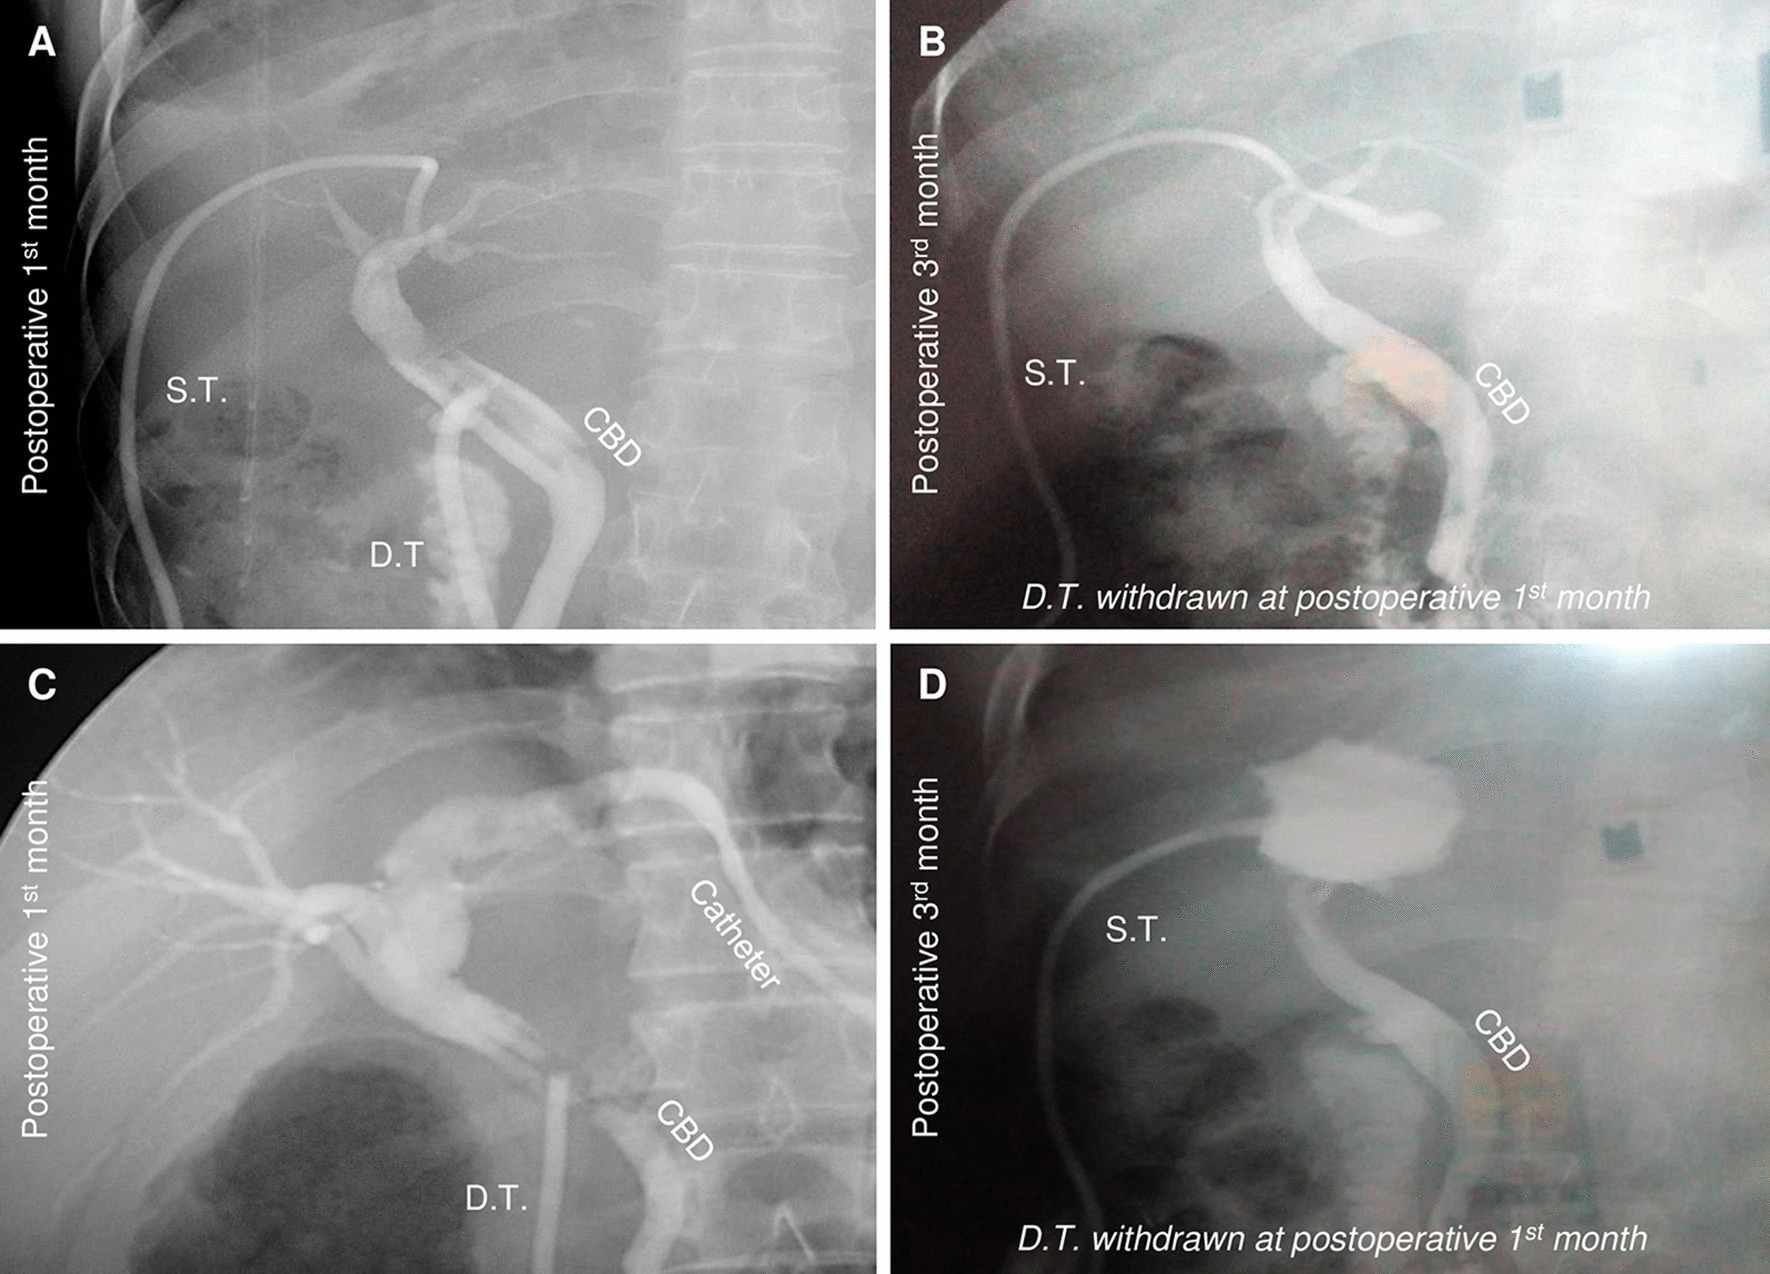

Postoperative T-tube removal

All subjects hold decompression T-tubes for about one month after cholangiographic examination was negative in both groups; and all sustaining T-tubes were removed if the results showed no leakage and indicates fully recover with the help of cholangiography at three months after the surgery in double T-tube drainage group (Fig. 5).